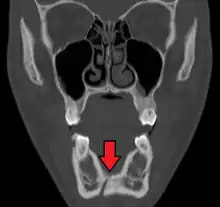

Computed tomography is the most sensitive and specific of the imaging techniques. The facial bones can be visualized as slices through the skeletal in either the axial, coronal or sagittal planes. Images can be reconstructed into a 3-dimensional view, to give a better sense of the displacement of various fragments. 3D reconstruction, however, can mask smaller fractures owing to volume averaging, scatter artifact and surrounding structures simply blocking the view of underlying areas.

Towne's view of a bilateral condyle fracture. White arrow is a fracture on the neck of the condyle. Black arrow shows the condyle pulled to the medial. The same injury can be seen on the opposite side